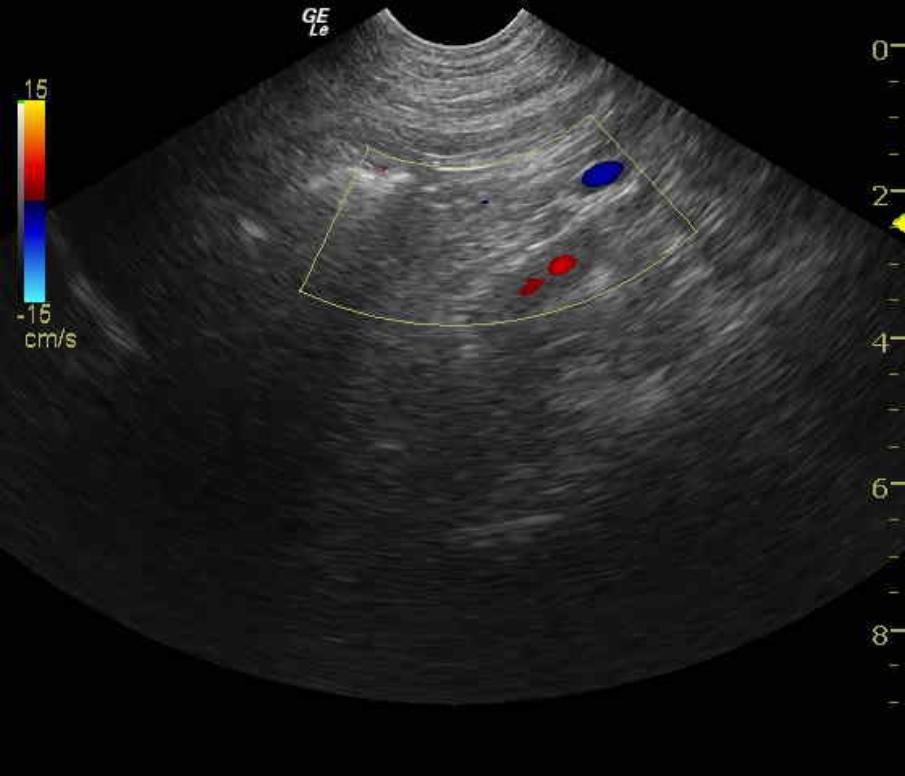

A 2-year-old FS Rottweiler dog was presented for lethargy, vomiting, and anorexia. The CBC demonstrated a leukocytosis consisting of a lymphocytosis, an eosinophilia, and a basophilia. Blood chemistry revealed azotemia, hyperphosphatemia, hyponatremia, and hyperamylasemia. The CBC and chemistry were repeated 3 days later and revealed persistence of the lymphocytosis. The serum biochemical profile revealed a decreased creatinine, hypoproteinemia, hypoalbuminemia, hyperkalemia, hypomagnesemia and hyperamylasemia.

A 2-year-old FS Rottweiler dog was presented for lethargy, vomiting, and anorexia. The CBC demonstrated a leukocytosis consisting of a lymphocytosis, an eosinophilia, and a basophilia. Blood chemistry revealed azotemia, hyperphosphatemia, hyponatremia, and hyperamylasemia. The CBC and chemistry were repeated 3 days later and revealed persistence of the lymphocytosis. The serum biochemical profile revealed a decreased creatinine, hypoproteinemia, hypoalbuminemia, hyperkalemia, hypomagnesemia and hyperamylasemia. The urinalysis showed a low specific gravity, and no bacterial growth was noted on the urine culture.